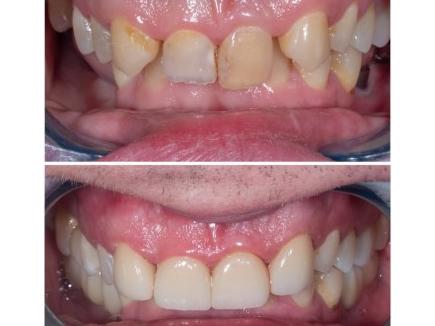

В данном клиническом случае мы показываем как можно эстетически подкорректировать врожденные аномалии. У пациента с рождения отсутствуют вторые резцы, их место заняли клыки.

Визуально мы видим несоответствие формы,  наличие промежуткав между зубами, а также дисколорит.

Было предложено исправить данный дефект с помощью коронок из диоксида циркония.

Результат понравился как пациенту, так и нам.